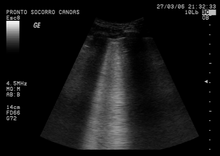

Ultrasound

Pulmonary ultrasound, performed at the bedside or on the accident scene, is being explored as a diagnosis for pulmonary contusion. Its use is still not widespread, being limited to facilities which are comfortable with its use for other applications, like pneumothorax, airway management, and hemothorax. Accuracy has been found to be comparable to CT scanning.[49]